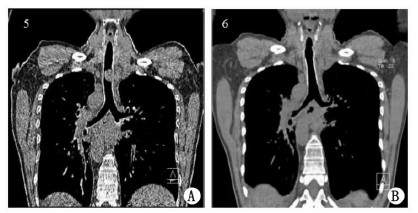

例2 患者男性,49 岁,因“确诊食管癌1年余,呼吸困难进行性加重1周”于2011年1月17 日入住邵逸夫医院。患者诊断食管癌1年余,曾行放疗1疗程,化疗7疗程。1周前出现气急进行性加重。体格检查:端坐呼吸,吸气时可见明显的三凹征,双肺双相干啰音,以胸骨柄处最明显。胸部CT:全内脏反位,气管中段腔内肿块,长约3 cm,管腔明显狭窄(图 2A)。入院后第2天患者呼吸困难进一步加重,面罩吸氧8 L/min下SpO2在 80%~85%,次日尝试支气管镜检查,患者根本无法耐受,气管镜连声门也进不了。遂选择ECMO支持下经支气管镜行气管支架植入术。采用股静脉-股动脉(V-A)模式,丙泊酚静脉麻醉镇静,循环系统预充:新鲜血浆100 mL,R-L液400 mL,肝素2 mg/kg,转流中监测MAP、SpO2。纤维支气管镜见气管中段管腔外压性狭窄伴腔内新生物,管腔基本堵塞,予顺利植入气管支架,镜下见原病变处管腔较前明显通畅。术后患者咳嗽气急症状明显缓解,1 d后复查胸部CT示:气管管腔通畅,支架位置良好(图 2B)。复查支气管镜:气管中段支架已完全张开,气管管腔通畅。随访1月无明显气急。

![]() |

| 图 2 A:术前胸部CT平扫加重建示,胸廓入口处T2椎体水平食管左侧肿块,侵犯前方并向气管内生长,气管腔部分狭窄。B:术后第3天胸部CT平扫加重建示,气管内占位已未见,气管支架植入,气管腔通畅,未见明显狭窄或新生物。 |